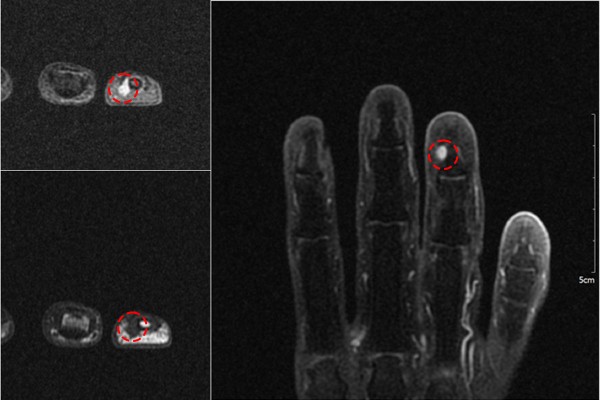

환자분의 손가락 상태를 자세하게 파악하기 위해서 MRI 촬영을 진행하였고, MRI 촬영 결과, 손톱 밑 부분에서 하얗게 신호 변화가 확인되었습니다.

측면에서 봐도 동그랗게 신호 변화가 확인되어 손가락 사구체종양(Glomus tumor 4th finger dist phalanx hand Rt.)을 진단하였습니다.